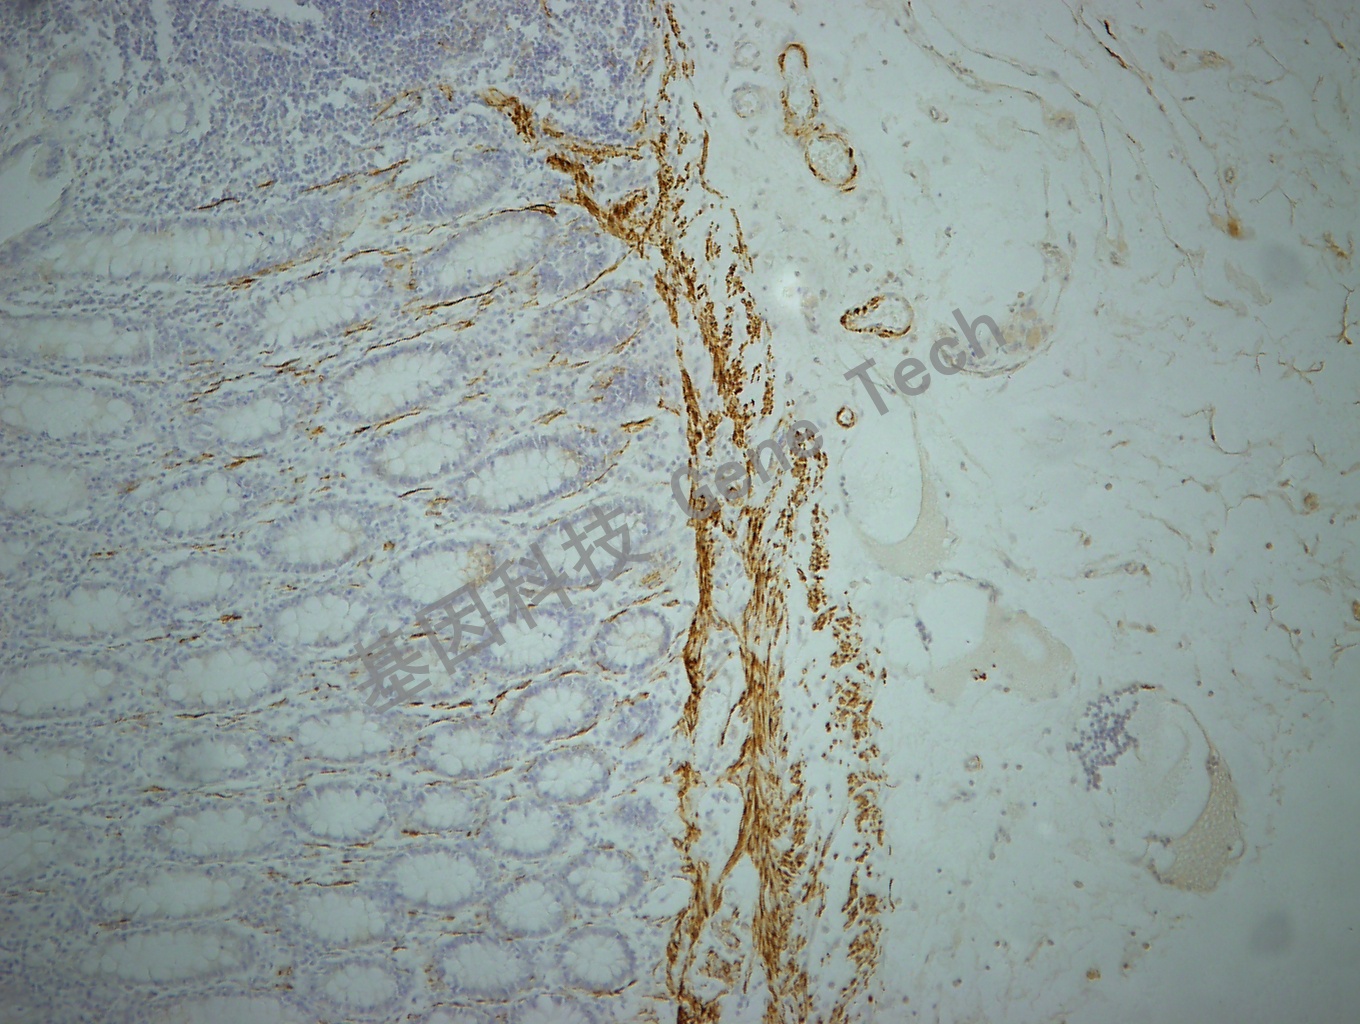

结肠癌石蜡切片,用 Desmin(GT2252)染色,细胞浆阳性,DAB 显色。